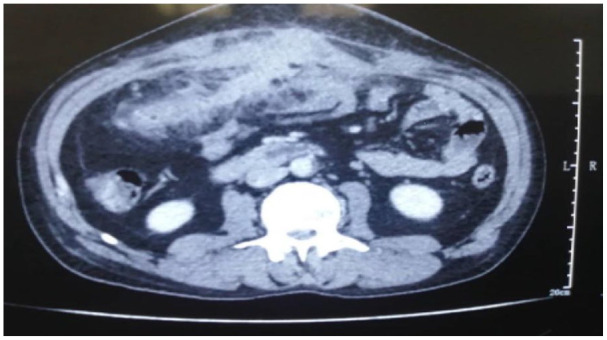

Actinomycosis is a rare chronic granulomatous infection caused by Actinomyces species. We report the case of a 47-year-old man with no previous medical history, who presented with a slowly growing abdominal mass extending to the abdominal wall, initially mimicking a malignant tumor. A diagnosis of an Actinomyces abscess was confirmed through surgical resection and histopathological examination. This case is presented to highlight the morphological characteristics and emphasize the diagnostic difficulties of this disease.